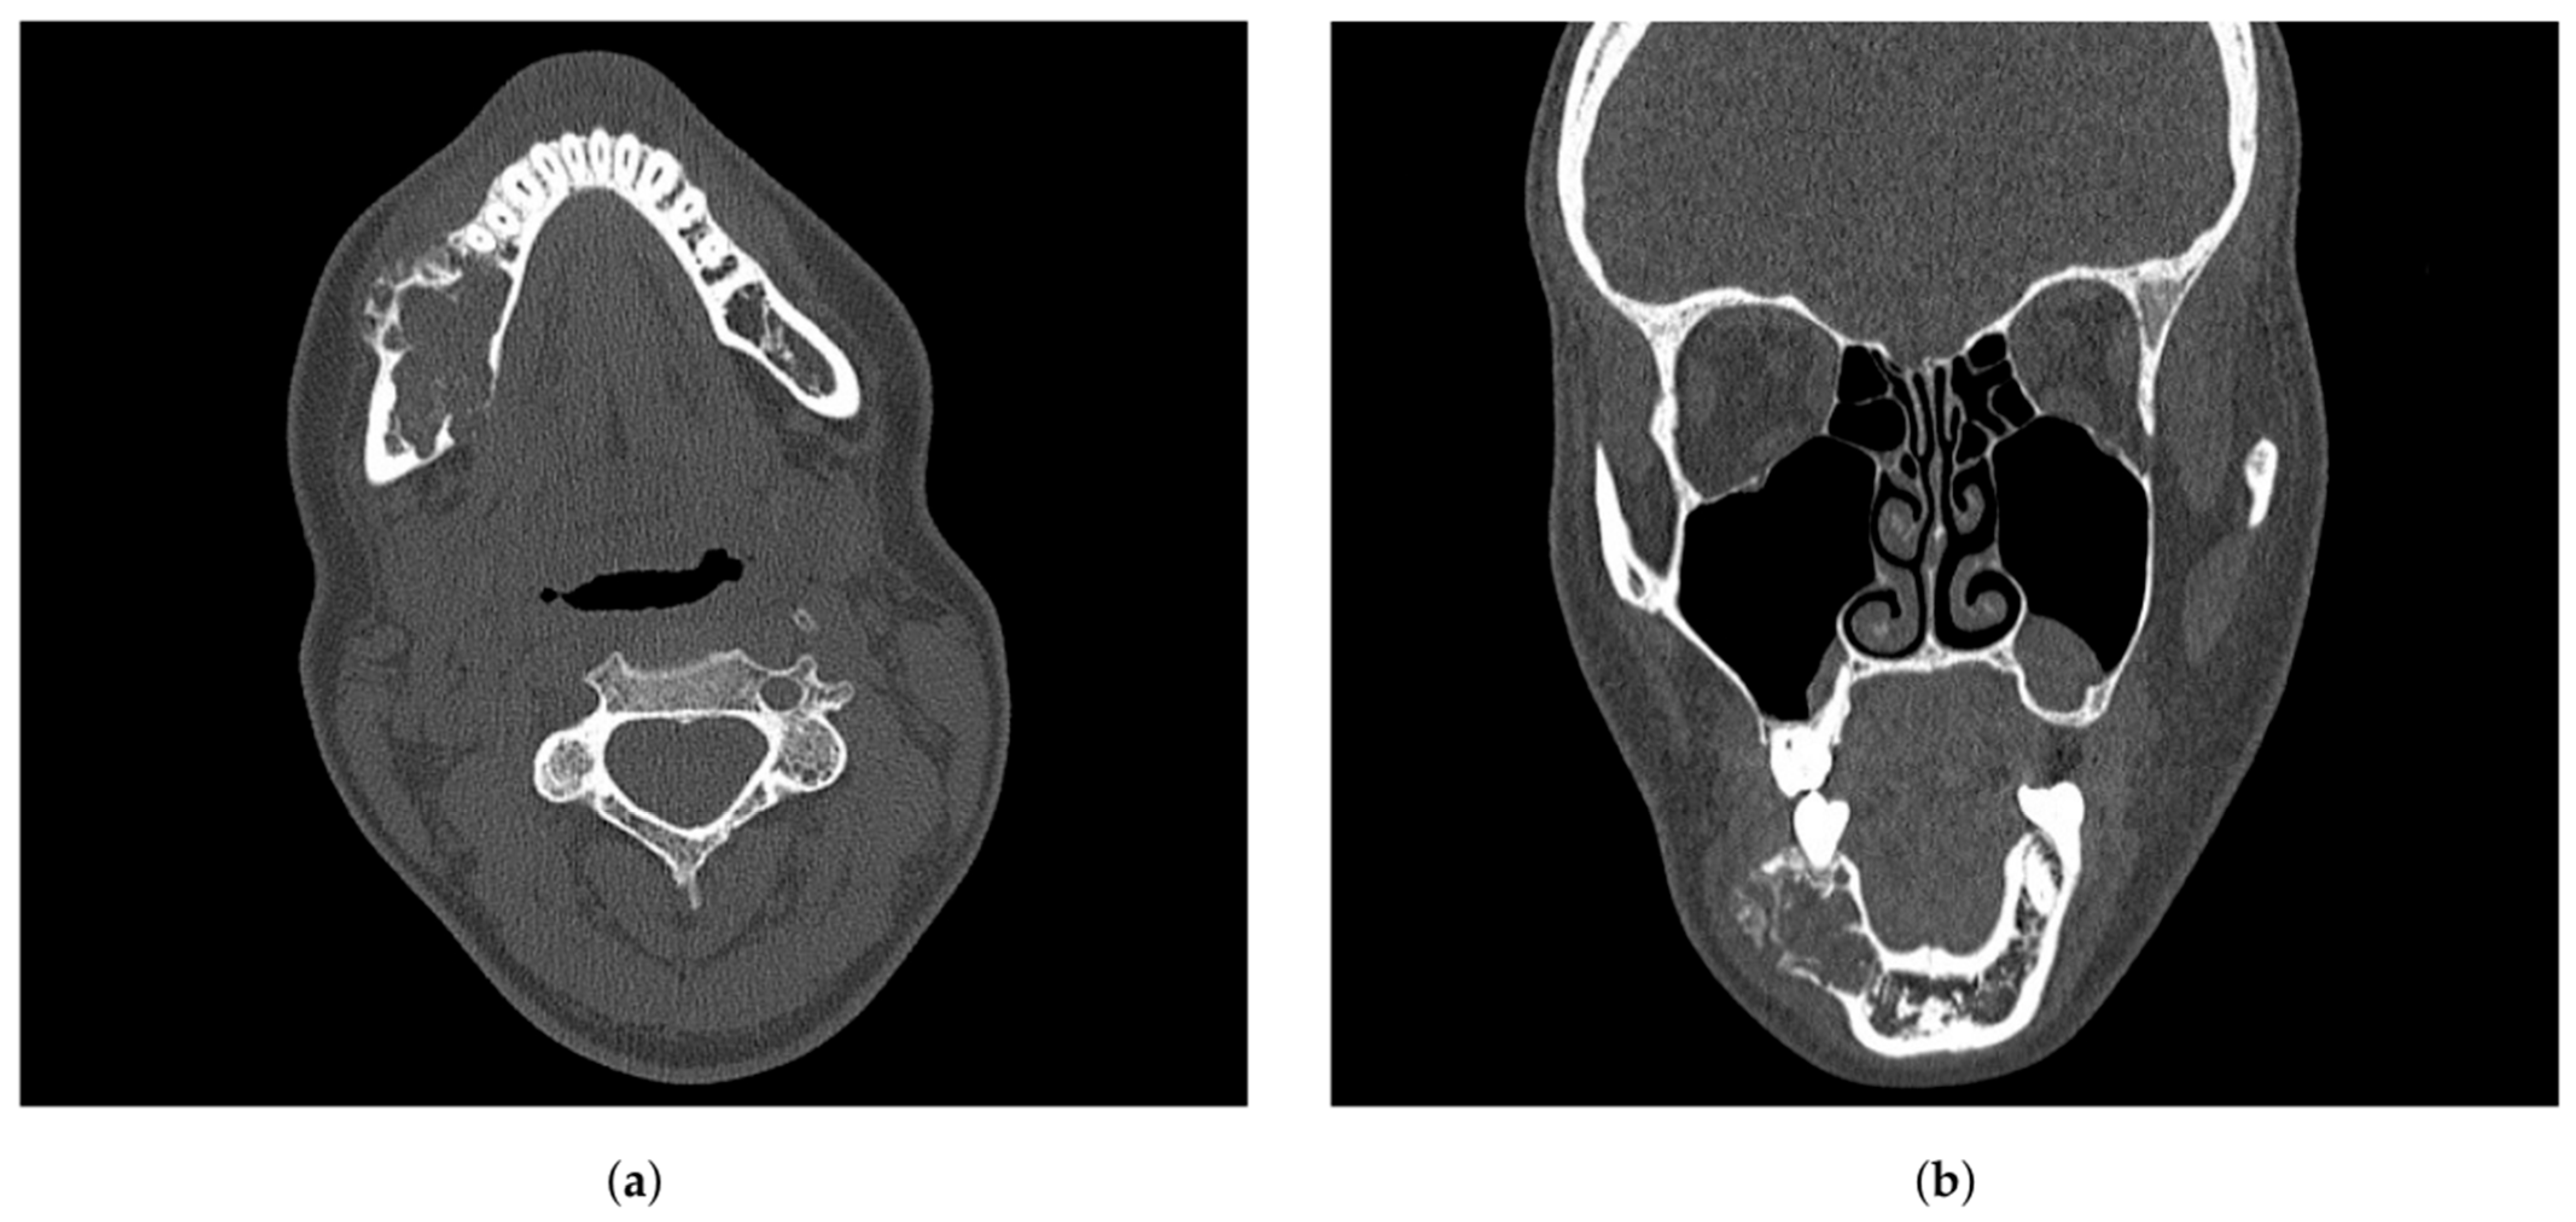

2.1. Examination

| Radiographic | “Soap-bubble”, “ground-glass” or “tennis racquet strings” patterns complicating the diagnosis | [4,12,14] |

| Radiographic Appearance | Multilocular radiolucency with “soap-bubble” or “honeycomb” pattern | Multilocular radiolucency, “soap-bubble” appearance | Eccentric, radiolucent lesion with cortical expansion | Ill-defined margins, may show soft tissue mass | Mixed radiolucent–radiopaque lesion, “sunburst” pattern |